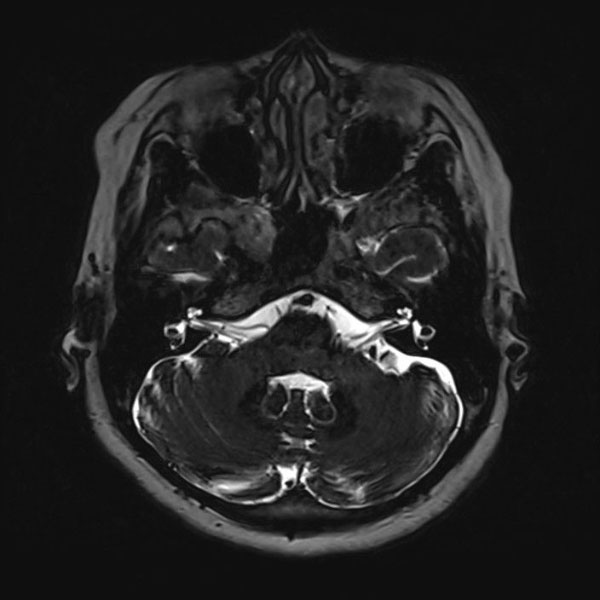

症例 '25年10月

No.

559

当院外来

'25年10月

50代

左顔面痙攣

(痙攣をとること)

手術前

減圧前

減圧後

術後血管撮影